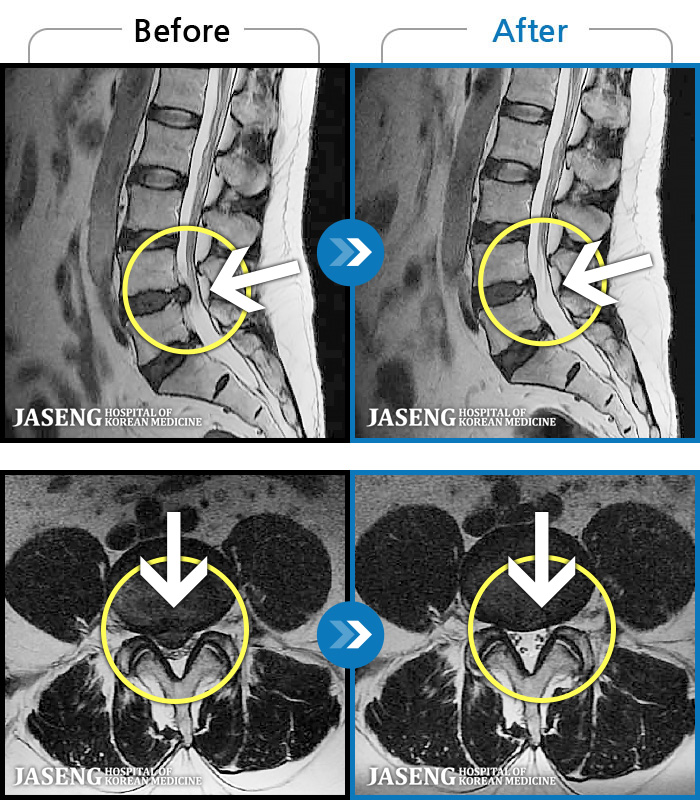

MRI ġ

1,240 MRI ũ ʸ Ȯϼ.